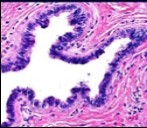

Figure 3.Ciliated cutaneous cyst with a coating of plump, ciliated columnar epithelium and a circumscribing fibro - connective tissue (12).

Typically, cutaneous ciliated cyst is a simple cyst which demonstrates a layering of pseudostratified ciliated columnar epithelium recapitulating conventional epithelial lining of the fallopian tube. As the cutaneous ciliated cyst demonstrates a morphological similarity to the fallopian tube lining epithelium, a Mullerian origin is indicated. Gross examination of cutaneous ciliated cyst depicts a solitary, mobile, non-tender, fluctuant, firm or soft to cystic lump with a fibrous wall and abundant amount of circumscribing adipose tissue. Cutaneous ciliated cysts are of a variable dimension. Cut surface usually displays a unilocular cyst impacted with clear, serous fluid, an attenuated smooth, greyish/ white cyst wall incorporated with incomplete septa traversing the cyst 6, 7.

Cutaneous ciliated cyst is layered with a singular layer of ciliated epithelial cells which are chiefly constituted by cuboidal to columnar epithelium, traversed by partially configured fibrous tissue septa with an admixture of randomly dispersed, intraluminal papillary projections akin to those cogitated in the fallopian tube. Superimposed epithelium is inundated with well vascularized, parallel bundles of collagen although smooth muscle is absent 7, 8.

Alternatively, cutaneous ciliated cyst can be lined by non ciliated cuboidal or columnar epithelium with intermingled intercalated, dark or round peg cells. Foci of squamous metaplasia can be occasionally exemplified in the adherent epithelium whereas mucinous cells or apocrine-like features are exceptional 6, 8. Figure 1, Figure 2, Figure 3, Figure 4, Figure 5, Figure 6, Figure 7, Figure 8, Figure 9, Figure 10, Figure 11, Figure 12. 11, 12, 13, 14, 15, 16, 17, 18, 19.